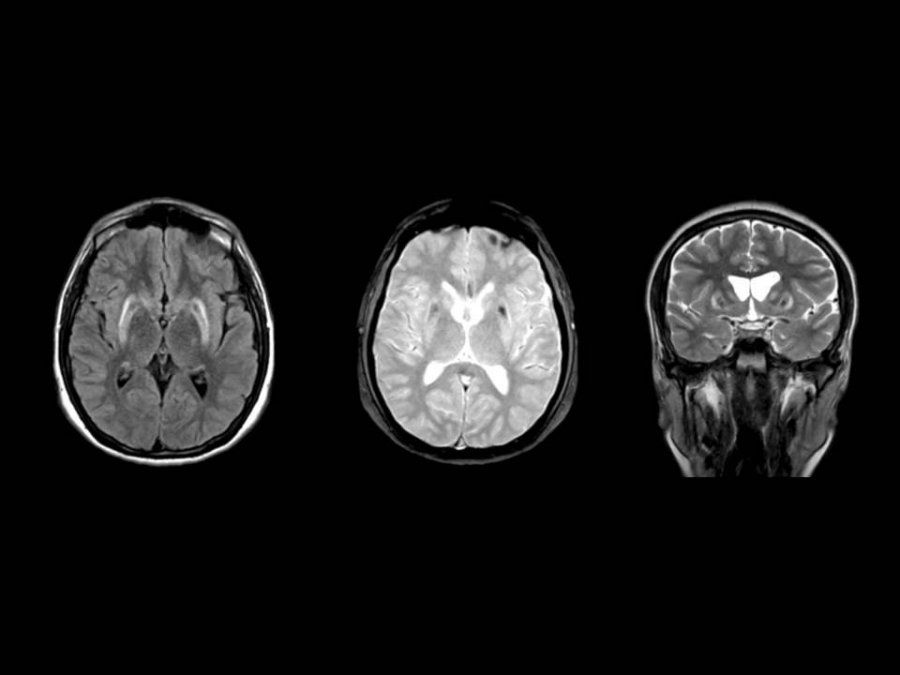

Síndrome de Hakim-Adams o hidrocefalia de presión normal, otra afección que puede atacar después de los 50

La enfermedad, también conocida como hidrocefalia de presión normal es de carácter neurológico. Por esta condición y los síntomas suele vincularse al Alzheimer, Parkinson, arterioesclerosis o síntomas propios de la senilidad.